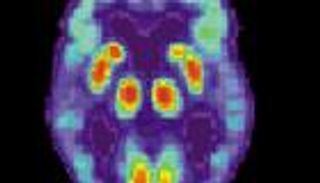

ومرض ألزهايمر هو الشكل الأكثر شيوعاً للخرف، وهو مصطلح شامل لعدد من الحالات التي تشمل تغييرات في الذاكرة والتفكير والحكم والتي تتعارض في النهاية مع استقلالية الشخص وقدرته على العمل.

وعلى الرغم من أن مرض ألزهايمر ليس له علاج حالياً، فإن هناك علاجاً واحداً، وهو عقار يسمى aducanumab (الاسم التجاري Aduhelm) الذي قد يبطئ التدهور المعرفي، وفقاً لجمعية ألزهايمر Alzheimer's Association.

ما الذي يسبب مرض ألزهايمر؟

يقول مركز السيطرة على الأمراض والوقاية منها: "لم يفهم العلماء بعد أسباب مرض ألزهايمر بشكل كامل، ومن المحتمل ألا يكون هناك سبب واحد ولكن هناك عدة عوامل يمكن أن تؤثر على كل شخص بشكل مختلف، والتي تشمل: